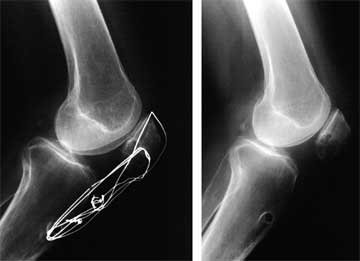

Serial lateral radiographs are taken to detect any decrease in patellar height for patients demonstrating limited patellar mobility or in whom an early arthrofibrotic response is detected. The height of the patella is measured as shown below.

On the left image, the numerator (line segment A) is the distance between the most ventral (anterosuperior) rim of the tibial plateau and the lowest end of the patellar articular surface. The denominator (line segment B) is the maximum length of the patellar articular surface. An alternative numerator (line segment C) locates the tibial reference point on the middle of the tibial plateau. The patellar vertical-height ratio equals A/B or C/B. Right, the numerator (A) is the superior most aspect of the trochlear cartilage that is in contact with line segment B. The denominator (line segment B) is the maximum length of the articular patellar surface. Using this method, the mean index is 32 + 12%, greater than 50% is a patellar infera, and less than 12% is a patella alta.